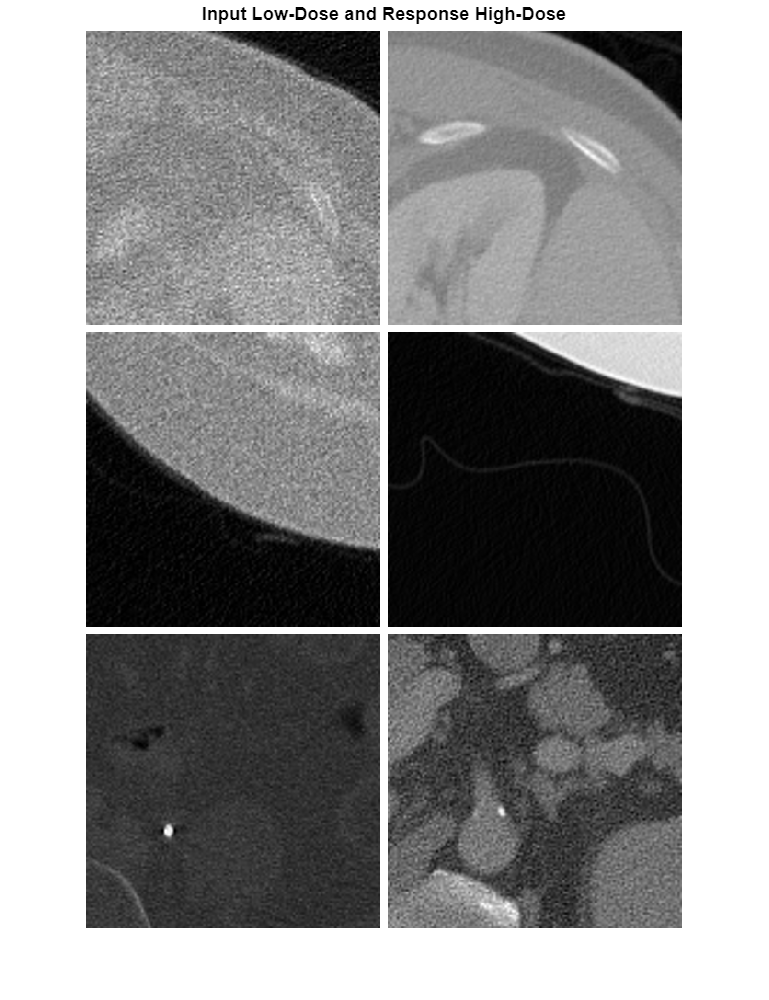

Visualize the low-dose and high-dose image patch pairs from the shuffled training set. Notice that the image pairs of low-dose (left) and high-dose (right) images are unpaired, as they are from different patients.

numImagePairs = 3;

imagePairsTrain = [];

for i = 1:numImagePairs

imLowAndHighDose = read(dsTrain);

inputImage = imLowAndHighDose.InputImage{1};

inputImage = rescale(im2single(inputImage));

responseImage = imLowAndHighDose.ResponseImage{1};

responseImage = rescale(im2single(responseImage));

imagePairsTrain = cat(4,imagePairsTrain,inputImage,responseImage);

end

montage(imagePairsTrain,Size=[numImagePairs 2],BorderSize=4,BackgroundColor="w");

title("Input Low-Dose and Response High-Dose");